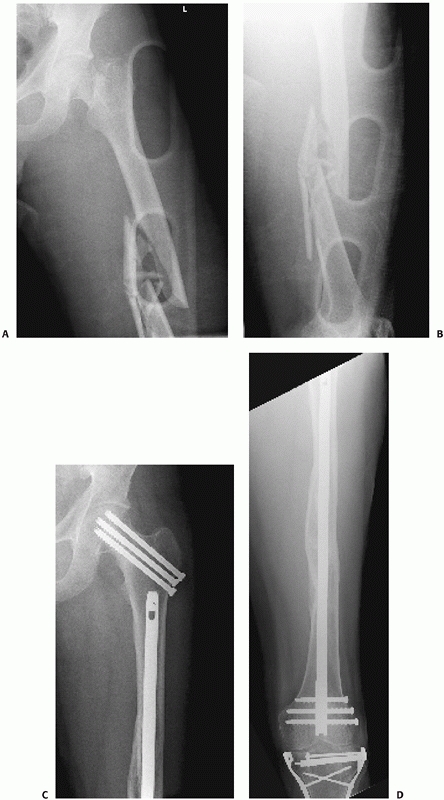

![]() |

FIGURE 50-10 Femoral plating for a simple fracture pattern. Plate length and screw position are more important than screw number.

FIGURE 50-11 This 74-year-old male sustained a periprosthetic femoral shaft fracture after a motor vehicle crash (A, B). He had no previous problems with his hip prosthesis. The femur was plated using an extensile lateral approach (C-F).

Given the spiral fracture configuration, a direct fracture reduction with lag screw fixation was performed. A long neutralization plate that spanned the entire femur was used. |